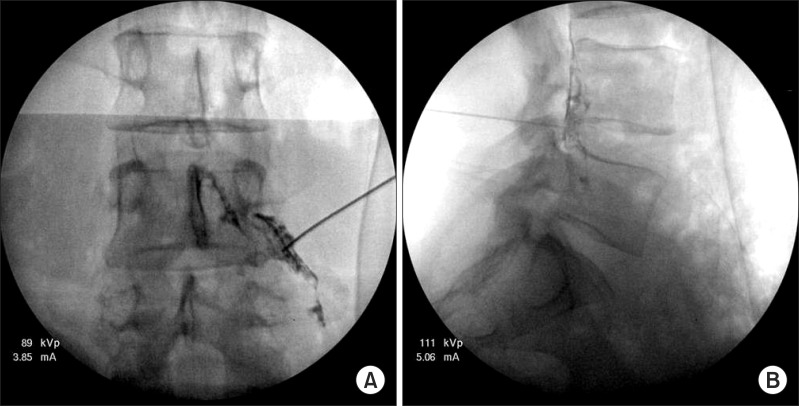

1. C-arm(투시 영상 장비)을 사용해 실시간으로 시술 부위를 확인하면서 시술을 진행합니다.

2. 철저한 멸균 소독을 시행한 후, 얇은 주사바늘을 신경이 나가는 추간공 부위에 정확히 위치시킵니다.

3. 조영제를 사용해 약물이 신경을 감싸는 경막외강(epidural space)에 제대로 들어갔는지 확인합니다.

4. 확인이 되면, 항염증제와 진통제 성분이 포함된 약물을 주입합니다.